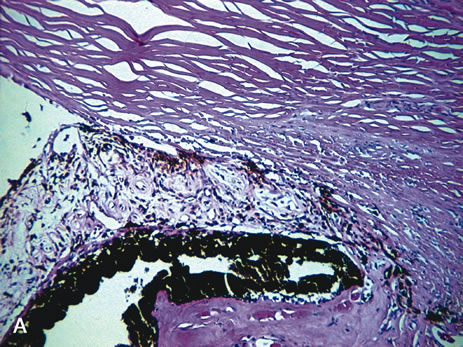

Iris changes resulting from diabetes can be seen histopathologically in proliferative diabetic retinopathy. Neovascularization may be seen on the anterior surface of the iris and may contract and pull the pigmented iris epithelium around the pupillary edge, creating ectropion uvea. Additionally, the neovascular membrane may grow over the trabecular meshwork, leading to neovascular glaucoma (Fig. 7A). Lacy vacuolization of the iris pigment epithelium may be seenhistologically if enucleation is performed during a hyperglycemic state. These intraepithelial vacuoles contain glycogen and are periodic acid–Schiff (PAS) positive. In addition, the basement membrane of the ciliary pigment epithelium may show diffuse thickening (Fig. 7B).44

Fig. 7. A. Neovascular glaucoma. The anterior chamber angle is blocked by peripheral anterior synechia. Neovascularization of the iris is present. (Hemotoxylin-eosin ×25.) B. Diabetes. The ciliary epithelium shows diffuse thickening of the basement membrane. (Periodic acid–Schiff ×35).